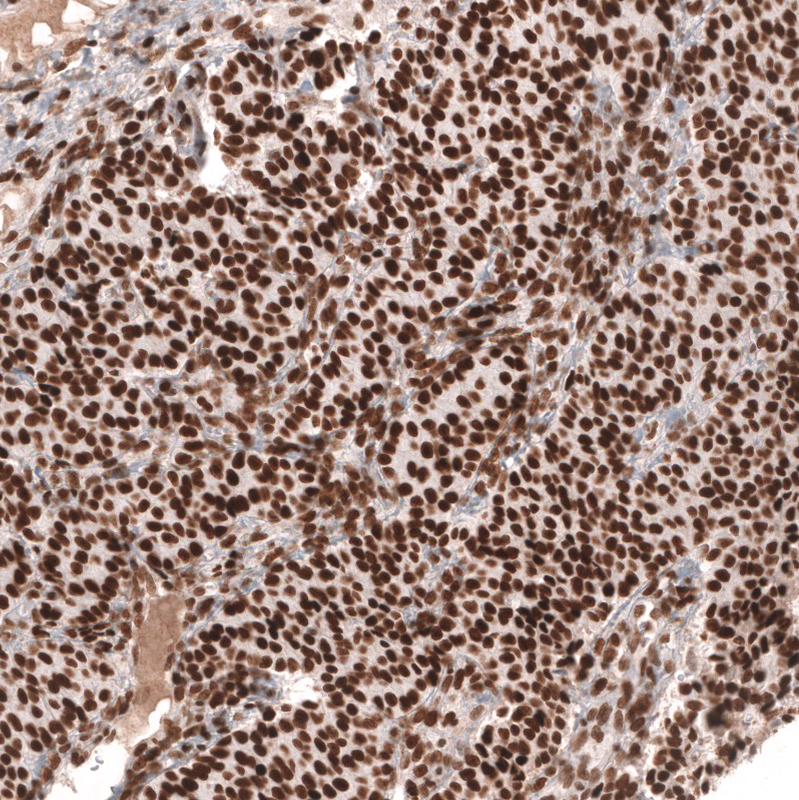

Immunohistochemistry analysis in human lymph node and skeletal muscle tissues using AMAb91894 antibody. Corresponding MSH2 RNA-seq data are presented for the same tissues.